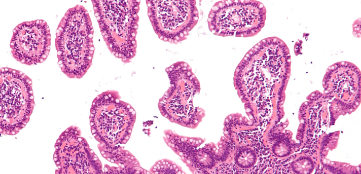

Hodgkin’s Lymphoma is named after Thomas Hodgkin, an English scholar and physician who described it in 1832. It is more common in older children and teenagers. Children younger than five years old are unlikely to suffer from this condition. An organ or lymph node affected by this type of lymphoma contains specific malignant cells known as Reed-Sternberg cells.

The term refers to all other types of lymphoma. As a child grows into adolescence, the incidence of non-Hodgkin's lymphoma increases. Non-Hodgkin's lymphoma is characterised by the malignant growth of lymphocytes (a type of white blood cell found in the lymph nodes). There is also malignant growth of lymphocytes in one form of leukaemia (acute lymphoblastic leukaemia, or ALL), which can make separating lymphoma from leukaemia difficult. Leukaemia is generally associated with extensive involvement of the bone marrow, whereas lymphoma has mild or no involvement.